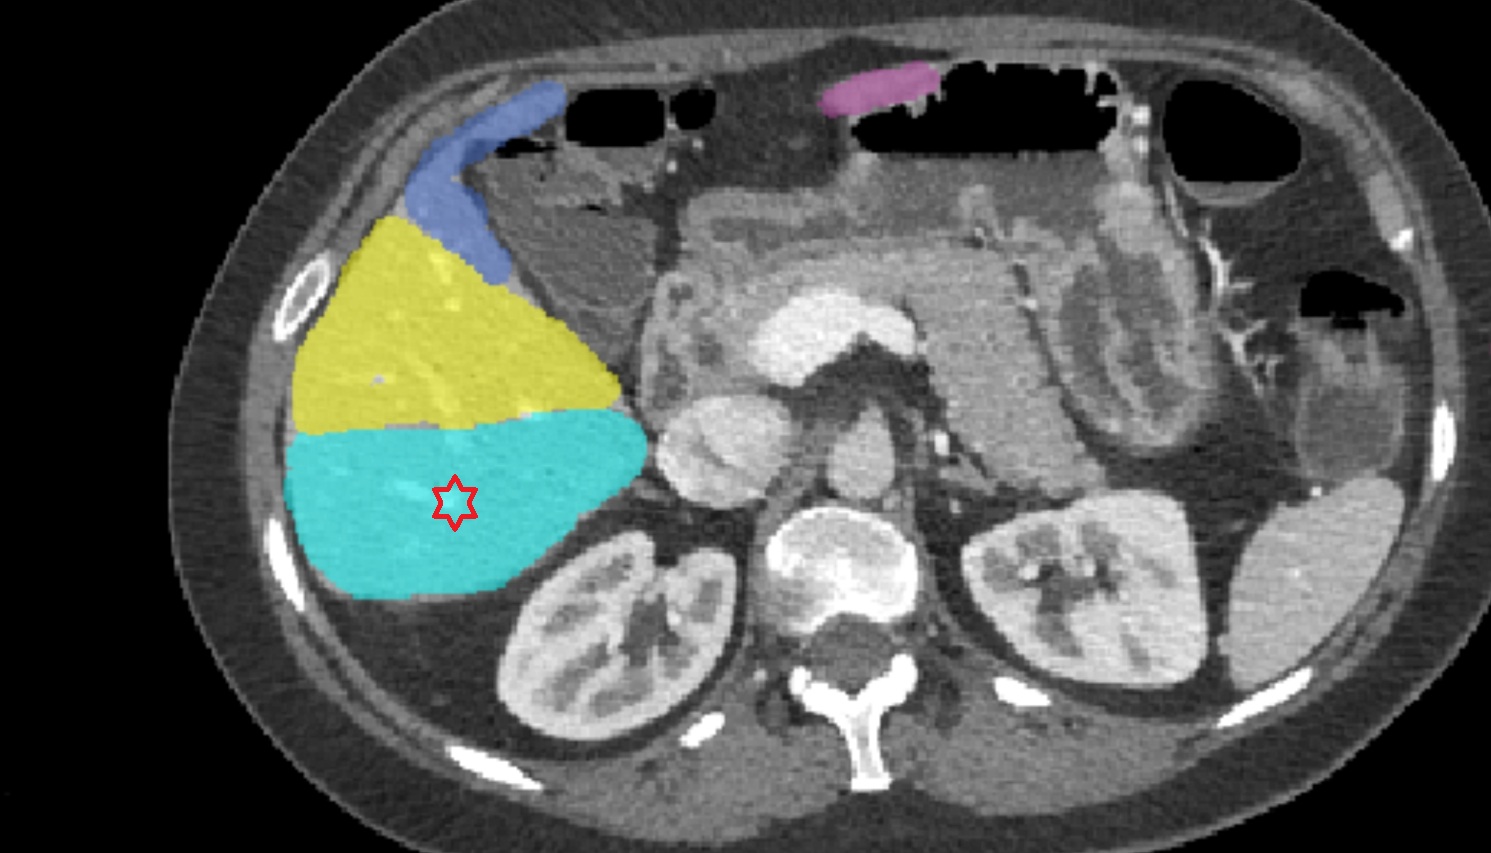

Liver right  posteroinferior segment — Segment VI   CT  axial  anatomy  image

CT image

Liver right posteroinferior segment — Segment VI CT axial image